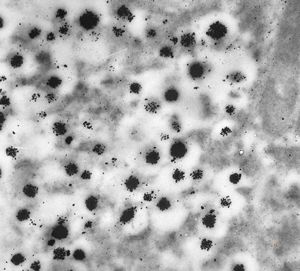

F,41y. | synovial metaplasia - capsule of implantate